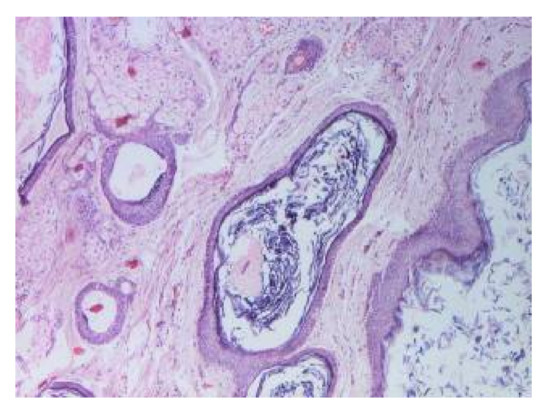

4.2. Histopathology Features